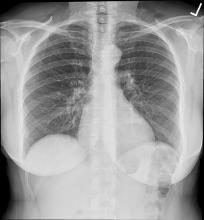

A new study finds that your fate may not be written in the stars, but instead hidden in plain sight in a chest X-Ray. Can one image predict your mortality?